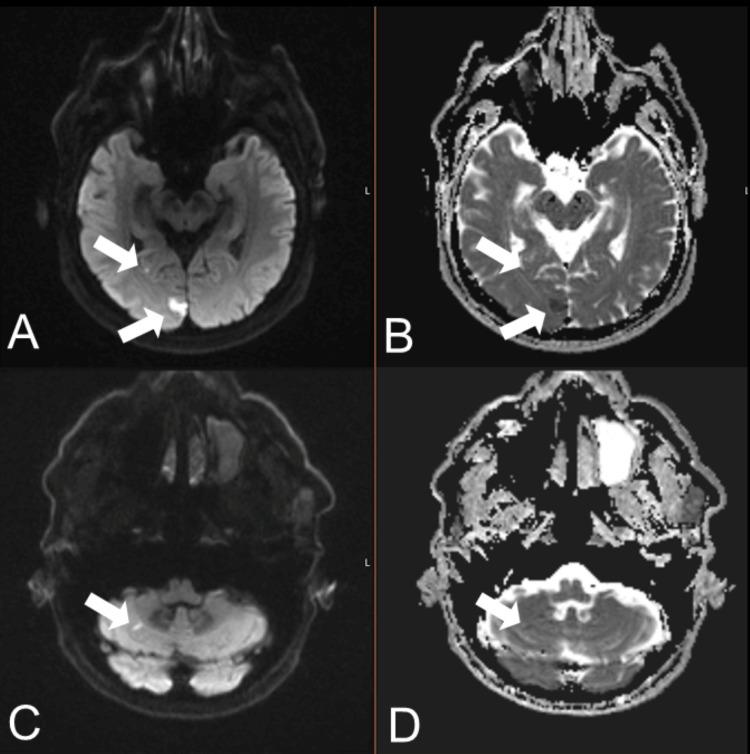

A 67-year-old man with a history of hypertension and untreated dyslipidemia presented with a four-day history of frequent episodic vertigo associated with nausea and vomiting. The patient experienced up to 20 episodes of spinning vertigo per day, each lasting several minutes, without provocation by head movement. MRI confirmed acute infarcts in the right posterior cerebral and cerebellar territories, and CTA revealed severe stenosis of the left vertebral artery V4 segment, with a hypoplastic right vertebral artery. Given refractory symptoms despite dual antiplatelet therapy and permissive hypertension, urgent intracranial balloon angioplasty and balloon-mounted drug-eluting stent placement was performed. The patient recovered completely without further dizziness or neurological deficit. This case emphasizes that recurrent atypical vertigo and brief syncope may be warning signs of vertebrobasilar insufficiency, especially in the context of vertebral artery stenosis with limited collateral flow. Timely vascular imaging and intervention can prevent subsequent debilitating brainstem stroke.

一名67岁男性,有高血压病史且血脂异常未治疗,出现了为期四天的频繁发作性眩晕,伴有恶心和呕吐。患者每天经历多达20次旋转性眩晕发作,每次持续数分钟,头部运动不会诱发。MRI证实右侧大脑后和小脑区域有急性梗死,CTA显示左椎动脉V4段严重狭窄,右侧椎动脉发育不全。尽管进行了双重抗血小板治疗和允许性高血压治疗,但症状仍难以控制,遂紧急进行了颅内球囊血管成形术和球囊载药洗脱支架置入术。患者完全康复,未再出现头晕或神经功能缺损。该病例强调,反复出现的非典型眩晕和短暂晕厥可能是椎基底动脉供血不足的警示信号,尤其是在椎动脉狭窄且侧支血流有限的情况下。及时的血管成像和干预可以预防随后使人衰弱的脑干卒中。